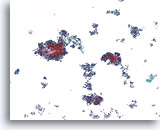

Lobulair carcinoom, Borst FNA, celblok.

Lobulaire carcinoomcellen lijken in het stromaweefsel te zijn ingebed, zodat de indruk wordt gewekt van hypercellulariteit. Dit kan de reden zijn waarom cytologische preparaten van een lobulair carcinoom vaak weinig maligne cellen tonen.

Lobulair carcinoom, Borst FNA, celblok.

Lobulaire carcinoomcellen lijken in het stromaweefsel te zijn ingebed, zodat de indruk wordt gewekt van hypercellulariteit. Dit kan de reden zijn waarom cytologische preparaten van een lobulair carcinoom vaak weinig maligne cellen tonen.

Lobulair carcinoom, Borst FNA, celblok.

Een enkele rij minimaal atypische spaarzame cellen die op en in de stromale fragmenten vastzitten, kan worden waargenomen. Let op de kenmerkende targetoïde intracytoplasmische vacuolen van lobulaire neoplasie.

Lobulair carcinoom, Borst FNA, celblok.

Een enkele rij minimaal atypische spaarzame cellen die op en in de stromale fragmenten vastzitten, kan worden waargenomen. Let op de kenmerkende targetoïde intracytoplasmische vacuolen van lobulaire neoplasie.